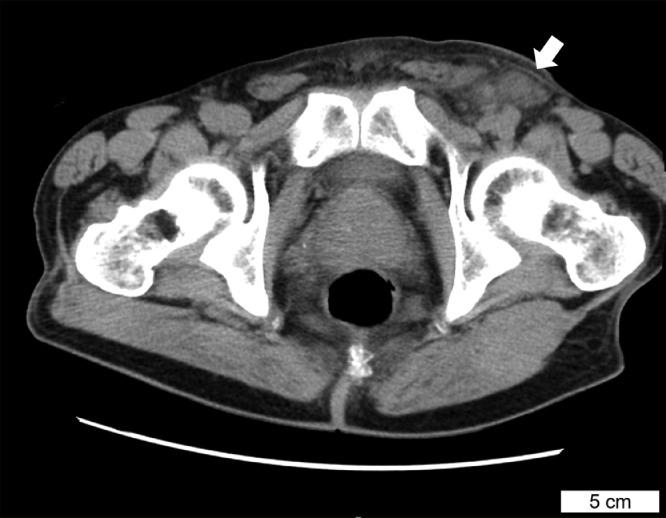

Syphilitic infection is usually observed in young patients, and the first stage of the disease (primary syphilis) is characterized by painless cutaneous and lymph node lesions. Herein, we describe a 71-year-old Japanese man with primary syphilis that presented as unilateral inguinal lymphadenopathy without skin lesions. Originally, an incarcerated hernia was clinically suspected. The lymph node pathologically showed suppurative lymphadenitis with vague granulomas; immunohistochemistry was highly suggestive of a syphilitic infection. Primary syphilis was confirmed by positive serological tests. Syphilitic infection should be included in the clinicopathological differential diagnoses for patients with inguinal lymphadenopathy, even in elderly patients without skin lesions.